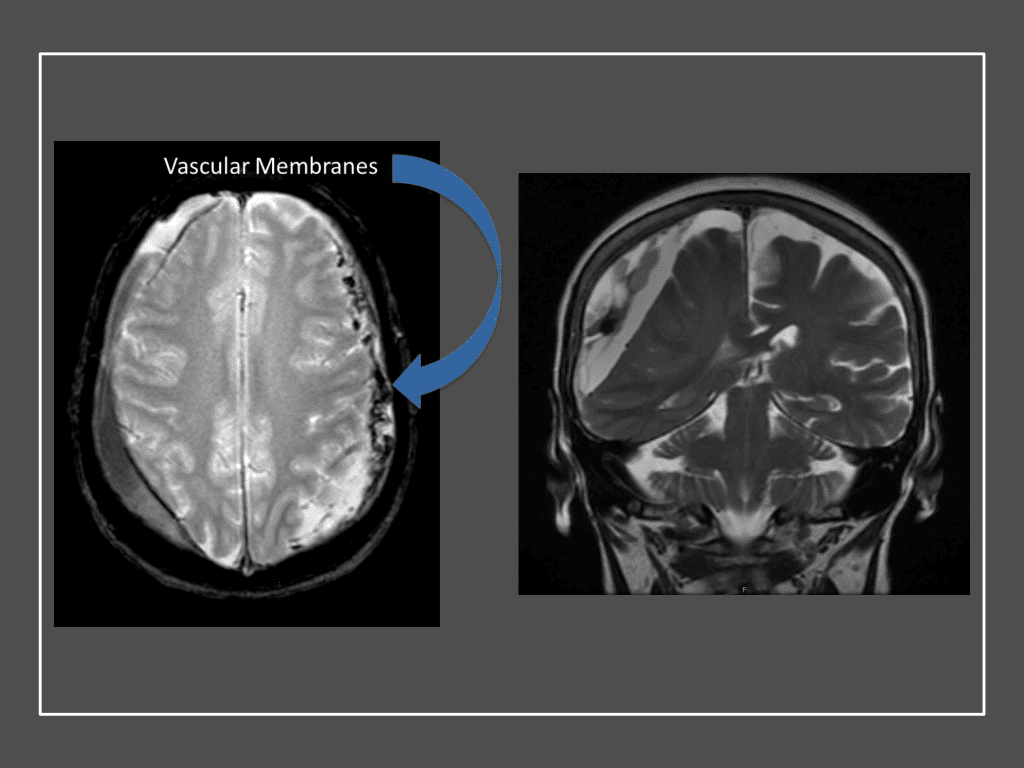

Clinically, the patient improved over the few weeks with the occasional transient twinge of a headache, but resolution of dizziness. Follow-up CT at 10 weeks demonstrated complete resolution of the bilateral subdural hematomas with our patient completely asymptomatic and back to all of her activities of daily living. Considering her history of thrombocytopenia and CLL, we will continue to monitor her into the future and are excited about her progress and recovery. (Figure 4. A and B)

Figure 4. A and B) – 10 weeks following embolization demonstrates complete resolution of bilateral collections both acute and chronic.

Figure 7. Neovascularized membranes within cSDH